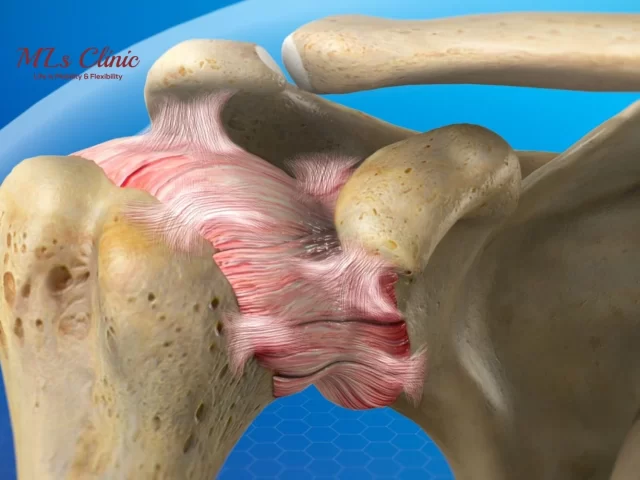

From Symptoms to Treatment for Frozen Shoulder: Relieving Shoulder Stiffness Effectively!

Are you suffering from constant Shoulder Pain? Even after showing to different doctors, your shoulder stiffness is not reducing? Or...

Shoulder Arthritis: Essential Do’s and Don’ts for Pain Relief

Shoulder Arthritis is one of the most common shoulder injuries rising these days. Many people ignore it initially only to...

5 Common Mistakes to Avoid During Shoulder Dislocation

Shoulder Dislocation refers to an injury in which the upper arm bone (Humerus) pops out of the shoulder blade socket....